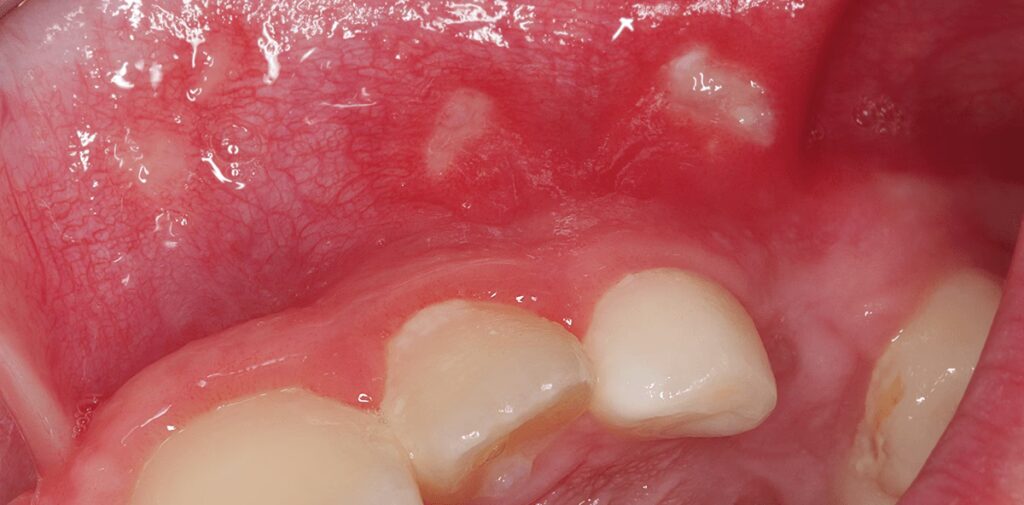

Aftøs Stomatitis (Blister eller After)

Dette er en af de mest almindelige former for mundsår. Blister er små, runde, smertefulde sår med en hvidlig eller gullig midte og en rød kant. De er ikke smitsomme, og den præcise årsag er ukendt, men man mener, at flere faktorer kan udløse dem, herunder: